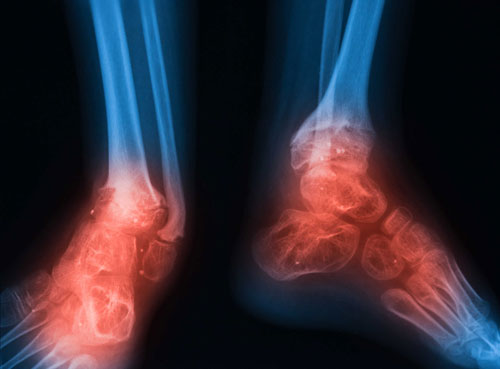

Afecțiuni osoase

– Fracturi osoase. Osteoblastele și osteoclastele sunt două tipuri de celule osoase care facilitează și stimulează reconstrucția țesutului osos afectat. Osteoclastele elimină țesutul osos afectat, permițând, astfel, osteoblastelor să producă țesut nou, care să-l înlocuiască pe cel eliminat. Terapia cu oxigen hiperbar stimulează funcțiile acestor celule, promovând vindecarea fracturilor. De asemenea, HBOT stimulează și formarea de noi vase de sânge care să permită alimentarea zonei cu oxigen, nutrienți, dar și celule imunitare care să lupte cu infecția din zona afectată.

– Osteomielită. Osteomielita este o infecție bacteriană cauzată de stafilococul auriu, ce afectează în special oasele lungi (femur, humerus, tibie). Tratamentul medicamentos cu antibiotice se poate prelungi și pe durata a câtorva luni. Deoarece stafilococii se dezvoltă în mediul anaerob, terapia HBOT este ideală în vederea opririi răspândirii infecției. Dacă tratamentul standard cu antibiotice nu are succes, infecția și inflamația pot bloca vasele de sânge. Când țesutul osos nu mai este alimentat cu oxigen, moare, determinând instalarea oseomielitei cronice.

Unii pacienți cu osteomielită au nevoie de intervenții chirurgicale adiționale față de tratamentul prelungit cu antibiotic. În aceste cazuri, tratamentele cu oxigen hiperbar pot ajuta chirurgii să determine cu exactitate zonele de infecție. De fapt, unii chirurgi recomandă HBOT pentru pacienți atât înainte, cât și după operație.

Au fost raportate și cazuri în care tratamentul cu oxigen hiperbar a fost eficient în cazul osteoporozei tranzitorii de șold. Boala este caracterizată prin edemul măduvei osoase a capului osului femural. Pacienții resimt dureri moderate sau severe, ce pot dura între 6 și 12 luni. Folosite cu succes și în cazul osteonecrozei capului femural, 25-29 sesiuni de tratament cu HBOT (4-5 ședințe pe săptămână) au accelerat procesele de recuperare ale pacienților diagnosticați cu osteoporoză tranzitorie.